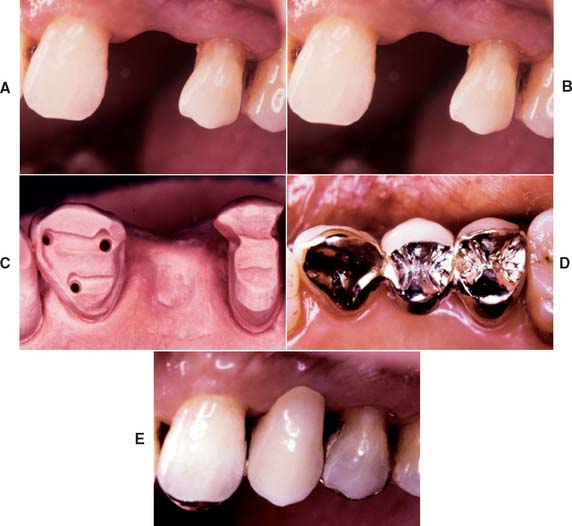

After placement and cementation of a fixed dental prosthesis (FDP), patient treatment continues with a carefully structured sequence of postoperative appointments designed to monitor the patient’s dental health (Fig. 32-1), stimulate meticulous plaque control habits, identify any incipient disease, and introduce whatever corrective treatment may be needed before irreversible damage occurs.

Fig. 32-1 Treatment after placement of multiple restorations. To ensure tissue health and long-term success, proper oral hygiene is mandatory.

To enable the dentist to monitor the function and comfort of the prosthesis and to verify that proper plaque control has been mastered by the patient (Fig. 32-4), an appointment is generally scheduled within a week to 10 days after the cementation of an FDP. The dentist should check carefully that the gingival sulcus remains clear of any residual luting agent that may have been overlooked previously and that all aspects of the occlusion remain satisfactory.

Fig. 32-4 Postcementation monitoring of plaque control is necessary around recently cemented restorations. Poor oral hygiene has led to gingival inflammation (arrows).